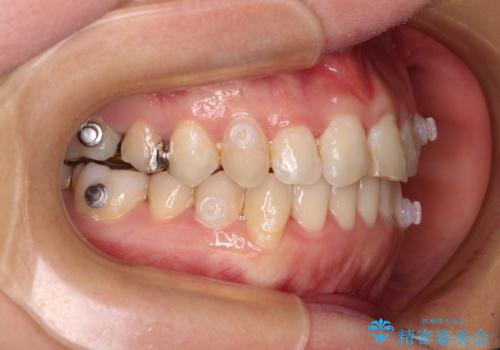

- 治療途中の奥歯の治療継続と、前歯のデコボコを気にして来院された患者様です。

根管治療まで終了している歯は症状がないため、より良好な咬み合わせを達成するために、矯正治療を行った後に補綴治療を行うこととしました。

下顎犬歯のクロスバイトが認められ、インビザライン矯正ではクロスバイト改善に伴い奥歯が噛みにくくなることが予想されたため、上下顎間ゴムを積極的に使用して咬み合わせの安定を図ることとしました。